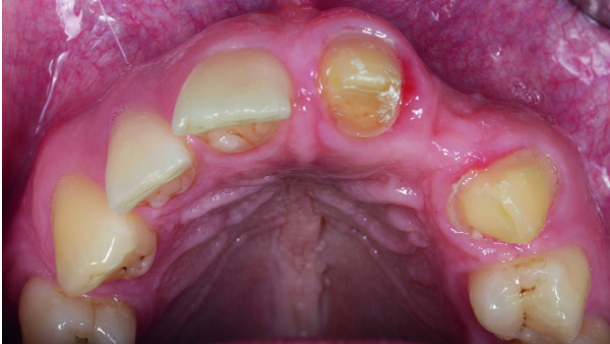

In the case presented, the treatment plan was to place a single implant in the aesthetically demanding anterior maxillary region in the place of the left lateral incisor.

A moderate horizontal ridge defect was present and the residual bone width was 5.6 mm. A staged approach employing a guided bone regeneration technique with a porcine partially demineralised cortical lamina (OsteoBiol Soft Cortical Lamina, Tecnoss Dental) was chosen. A porcine bone substitute (OsteoBiol mp3, Tecnoss Dental) was used as a filler material.

After the augmentation procedure, the lamina was covered with a collagen membrane to allow for rapid soft-tissue integration. The augmentation surgery was completed with meticulous flap closure using microsurgical techniques.

After a healing period of six months, an implant of 3.8 mm in diameter and 11 mm in length was placed according to the restorative planning. Finally, an all-ceramic crown was seated on the zirconia abutment.

The images of the final result demonstrate clearly that an aesthetically pleasing outcome was achieved by employing the bone augmentation technique described.